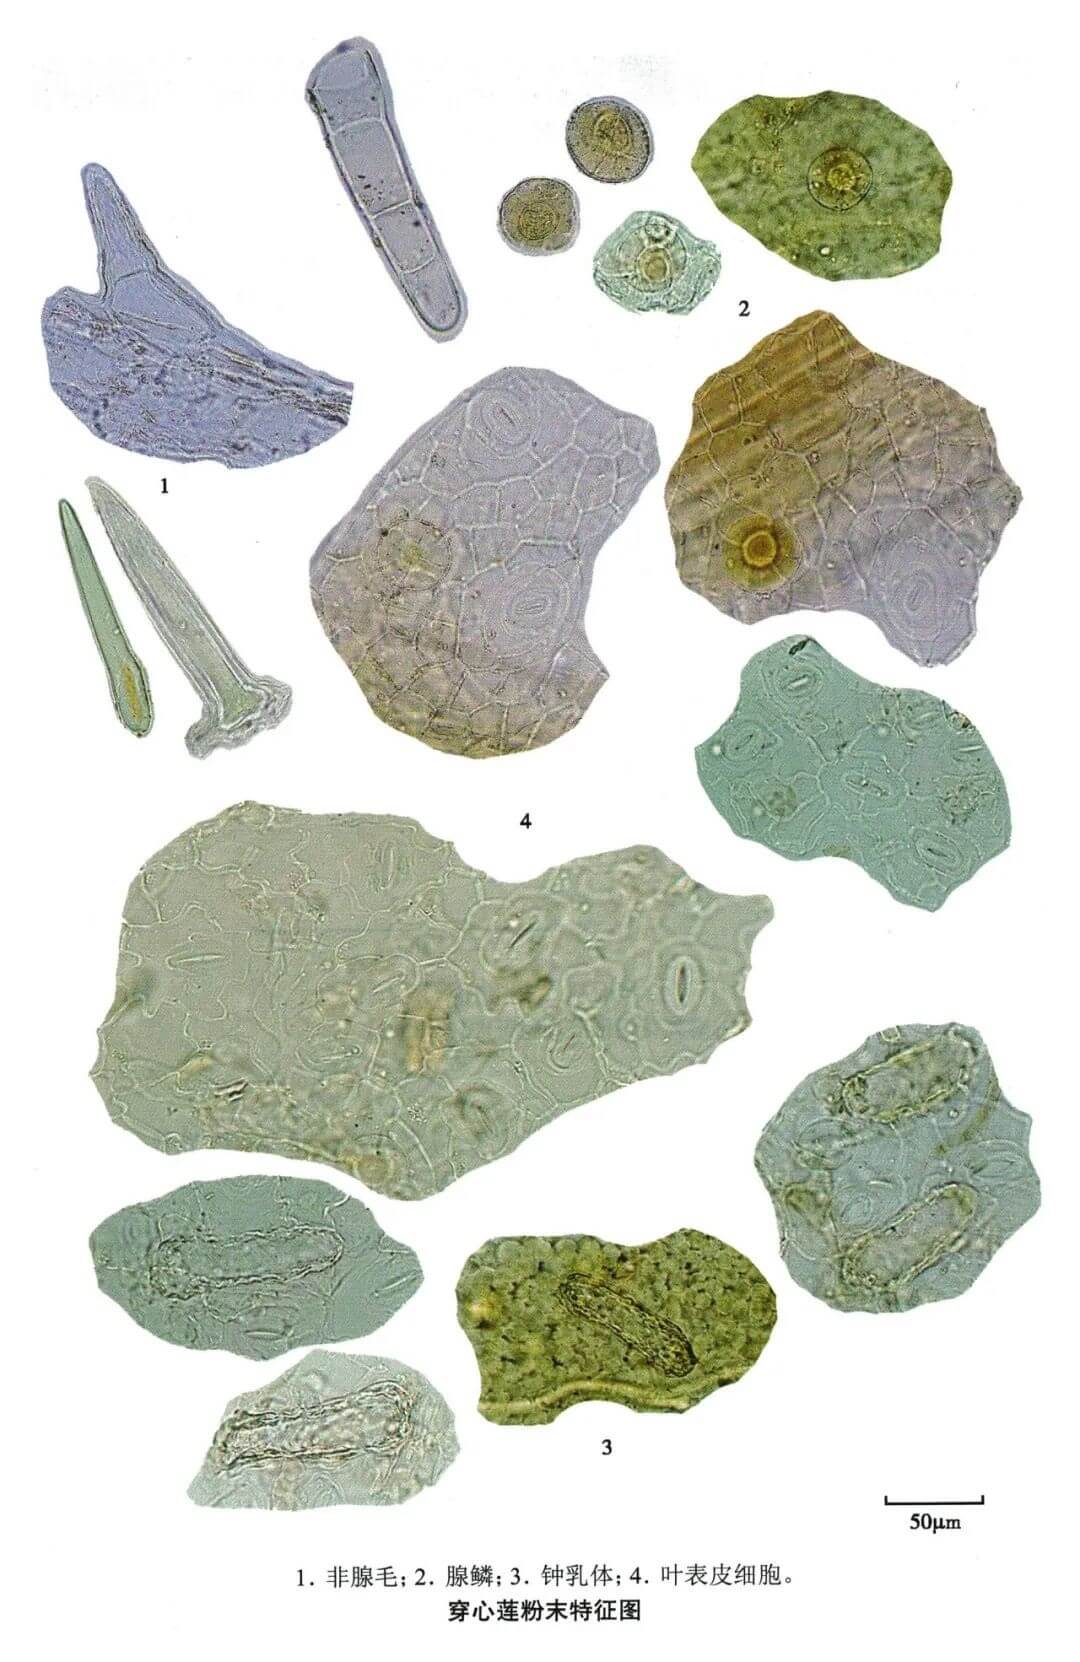

穿心莲

| 穿心莲 |

|---|

| 【参考文献】 《中药鉴定学》(康廷国主编) |

| 【显微鉴别】 粉末鲜绿色。上下表皮均有增大的晶细胞,内含大形螺状钟乳体,直径32 ~ 67μm,较大端有脐样点痕,层纹波状。气孔直轴式,副卫细胞大小悬殊,少数为不定式。腺鳞头部扁球形,4、6或8细胞,直径27 ~ 33μm,柄仅3μm。非腺毛1~4细胞,长至160μm,基部直径至40μm,有的具角质线纹。 |

| 【显微重点】 钟乳体。钟乳体存在于叶表皮及茎表皮细胞,穿心莲药材存在叶脱落或被人为去除等情况,因此有时难以观察到叶的显微特征。 |

| 【图谱来源】 《中药成方制剂显微图典》 |